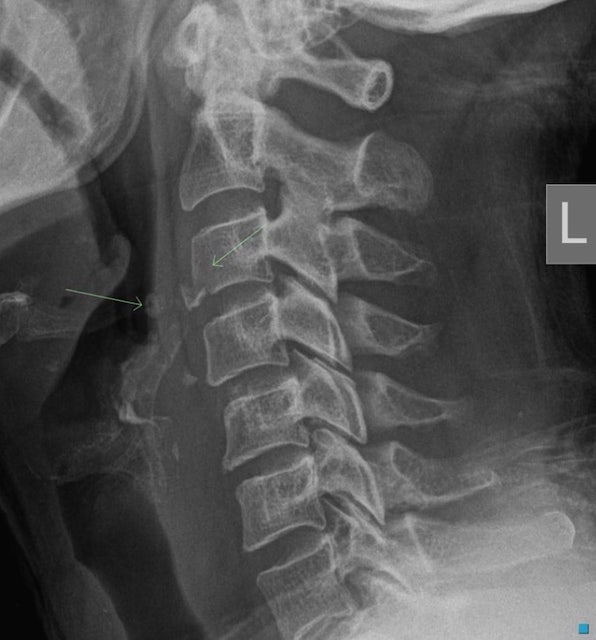

Gãy Hangman (Gãy qua eo C2)

- Gãy hangman (hangman’s fracture, gãy xương của người treo cổ) là gãy các thành phần sau của C2. Gãy xương của người treo cổ là do chấn thương quá duỗi- nén ép thường xảy ra trong tai nạn xe mô tô khi người lái đập trán vào kính chắn gió.

- Gãy qua eo C2 được quan sát rõ nhất ở phim chụp nghiêng cột sống cổ trên X quang thường quy và các lát cắt đứng dọc trên CT.

- Gãy loại này thường làm tách phần sau của thân đốt sống C2 khỏi phần trước của C2, làm cho phần trước của C2 bán trật ra phía trước trên thân của C3 (Hình 16).

- Một số trường hợp gãy qua eo C2 ít bị di lệch hơn và có thể cần chụp CT để phát hiện.

- Bởi vì gãy qua eo C2 dẫn đến làm rộng ống sống, chúng thường không gây tổn thương thần kinh. Điều này trái ngược với chấn thương mà loại gãy xương này được đặt tên, gãy xương khi bị treo cổ. Khi bị treo cổ, hiện tượng quá duỗi cổ gây gãy C2 và sự kéo tách C2 khỏi C3 do bị treo làm kéo cả tuỷ sống.